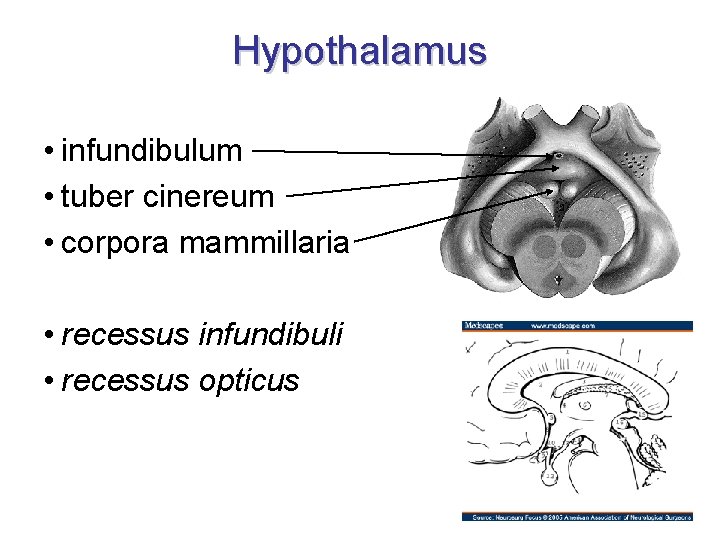

Hypothalamus • infundibulum • tuber cinereum • corpora mammillaria • recessus infundibuli • recessus opticus

Hypothalamus – ohraničení • • nahoře: sulcus hypothalamicus dole: viditelný na dolní ploše mozku vpředu: lamina terminalis vzadu: přechází do tegmentum mesencephali • mediálně: 3. komora • laterálně: capsula interna